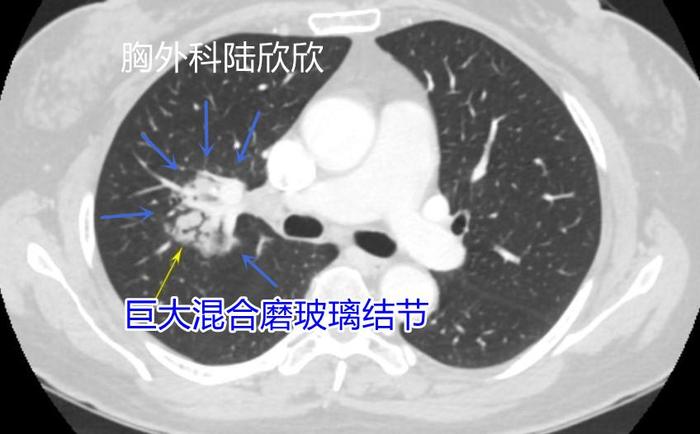

三、领结形或葫芦形磨玻璃结节

这个混合磨玻璃结节长得像一个领结形或葫芦中间通过一个狭窄的桥相连。病理是浸润性腺癌,含有微乳头亚型,恶性的很高。